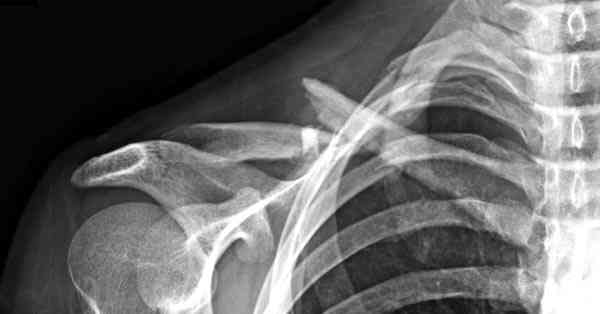

Описанный случай это больная моего партнера, мы недавно случай разбирали на нашей конференции (Morbidity and Mortality Conference аналог клинического разбора)

Выставлен как пример, к чему может привести

неудачно выбранный фиксатор.

Больные иногда пропадают из нашего поле зрения, ту больную неудачно оперировал в нашем городе специалист по спортивной медицине. Он же направил к нам после удаления фиксатора.